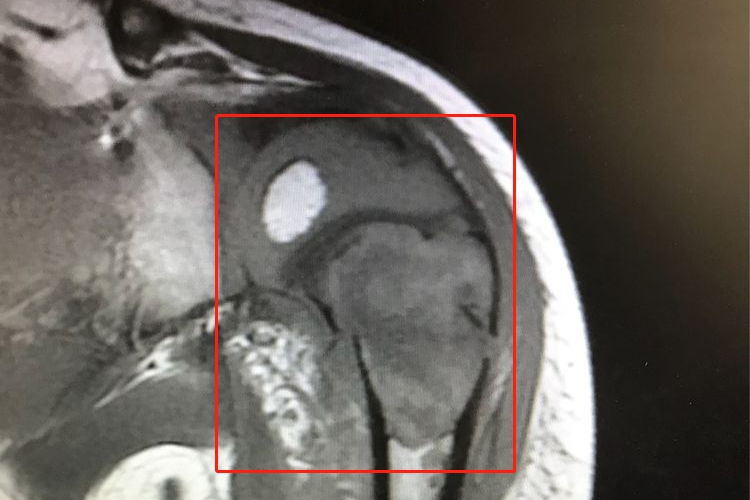

好发于股骨下端、胫骨上端、肱骨近端干骺端内。临床表现为疼痛、局部肿胀,如肿瘤累及邻近的关节,使关节出现不同程度的功能受累,表现为屈伸疼痛和受限,以及跛行等。影像学检查可见骨质破坏。